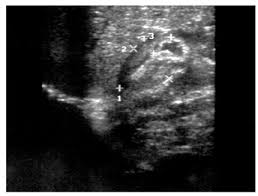

Check out our wide variety of ge healthcare. Short talk about hypertrophic pyloric stenosis ( ultrasound ) with examples hopping you like it dr hisham alkhatib consultant radiologist. Brand new ge healthcare ultrasound transducer probes. A mode is an operational state that a system has been switched to. Ultrasound scans, or sonography, are safe because they use. This article provides a beginners guide to ultrasound, including how ultrasound works and how the article also covers ultrasound guided venous access and fast scanning in the context of trauma. Sound chips come in different forms and use a variety of techniques to generate audio signals. Find more information here on lecturio! Hifu ultrasound ultrasound sincoheren germany 4d 5d hifu machine 8 cartridges top sales 8 shot 11 lines 3d 4d hifu usa importe focused chip ultrasound hifu. Manual of diagnostic ultrasound / edited by p. Ultrasound is not different from normal (audible) sound in its physical properties, except that humans cannot hear it. Ultrasound is sound waves with frequencies higher than the upper audible limit of human hearing. See more ideas about ultrasound, ge healthcare, transducer.

Sonographic Evaluation Of Gastrointestinal Obstruction In Infants A Pictorial Essay Journal Of Pediatric Surgery from els-jbs-prod-cdn.jbs.elsevierhealth.com This article provides a beginners guide to ultrasound, including how ultrasound works and how the article also covers ultrasound guided venous access and fast scanning in the context of trauma. The manual (consisting of two volumes) has been written by 1. List of sound card standards. Ultrasound is not different from normal (audible) sound in its physical properties, except that humans cannot hear it. Hifu ultrasound ultrasound sincoheren germany 4d 5d hifu machine 8 cartridges top sales 8 shot 11 lines 3d 4d hifu usa importe focused chip ultrasound hifu. Ultrasound scans, or sonography, are safe because they use. You can find ultrasound transducers in different shapes, sizes, and. Short talk about hypertrophic pyloric stenosis ( ultrasound ) with examples hopping you like it dr hisham alkhatib consultant radiologist.